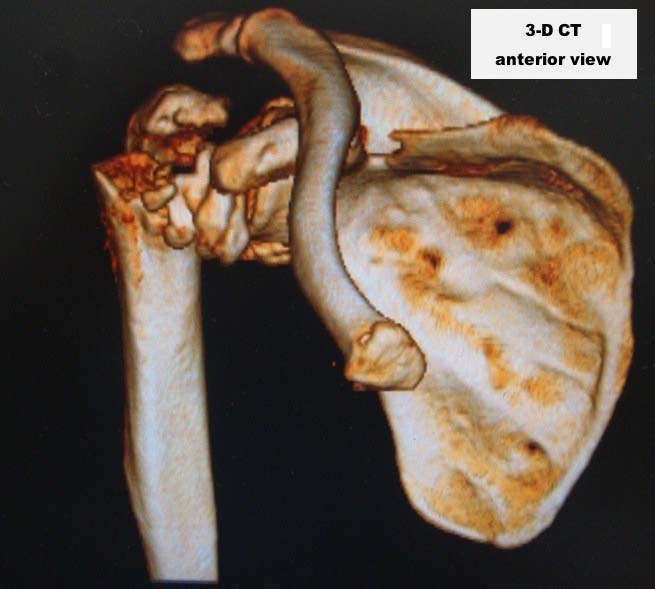

Here are some photos, of chronic, locked, 4 part posterior dislocation, 2 months old, that I did September/2011. Patient is 67, very, very active - had a really reasonable, honest clinical result ...

Photos attached ...